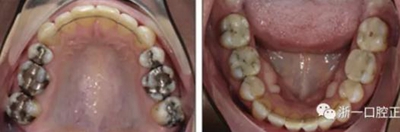

患者曾行正畸治療,現覺笑容不美觀前來就診?;颊哒嬗^及側貌示下頜發(fā)育不足,偏高角,唇閉合不全。上下頜中線齊。覆合、覆蓋4毫米。磨牙關系及尖牙關系II類。上頜擁擠度4mm,下頜擁擠度6mm。4顆第一前磨牙在第一次正畸治療時已拔除。上下牙弓呈尖圓型,牙弓狹窄。

由于下頜中切牙間沒有間隙行下頜正中切開術,故進行術前正畸擴展間隙。下頜前牙粘托槽,中切牙托槽成交放置,將中切牙牙根分開。使用0.018X0.018鎳鈦絲及置于下頜左、右中切牙之間的推簧推間隙。3個月后拍攝CBCT示已有足夠間隙行下頜正中截骨術。

全麻下進行上頜骨腭中縫骨皮質劈開及下頜正中劈開術。手術后,用X光片檢查上頜骨和下頜骨中線切口的位置和方向。

術后第9天開始旋轉擴弓器,每天轉2次,每次轉90度,即擴開0.5mm。每隔1周進行檢查,目標上頜擴開9mm,下頜擴開6mm。18天后,上頜中切牙間出現8mm間隙。下頜出現6mm間隙,(于13天出現后,停止旋轉擴弓器)。在擴弓器旋轉3天后,拍片發(fā)現左下頜中切牙遠中牙根中段有一條低密度陰影,臨床冷熱診反應遲鈍,可能為術中損傷所致。牙體牙髓科會診,建議行根管治療,故行根管治療。

擴弓保持8周后,除擴弓器影響牙外粘接托槽,使用0.014鎳鈦絲進行排齊、整平。旋轉停止后3個月拆除擴弓器,全口粘接托槽,使用0.016niti繼續(xù)排齊整平。佩戴可摘保持器,保持上頜寬度。在使用至0.018x0.018niti7周,徹底排齊整平后,使用大弓型的0.016x0.022不銹鋼絲,繼續(xù)維持原有寬度,同時停止使用可摘保持器。掛II類牽,糾正磨牙關系,使用鏈圈關閉散在間隙,少量使用IPR去除局部前牙的黑三角。術后9個月拍全景示,牙根平行度可,再無其他牙根出現問題。1年7個月后治療結束。上下頜3-3舌側保持器+哈雷氏保持器進行保持。

治療結果:

患者側貌改善,下唇唇肌緊張消失,上下唇可自然閉合。磨牙及尖牙關系糾正至I類,覆合覆蓋正常。上下頜弓型糾正至卵圓形,牙弓寬度增加。頭影測量分析示SNA角81.8°,ANB角3°。頭影測量重疊圖示下頜骨向后旋轉,垂直面高度略有增加。